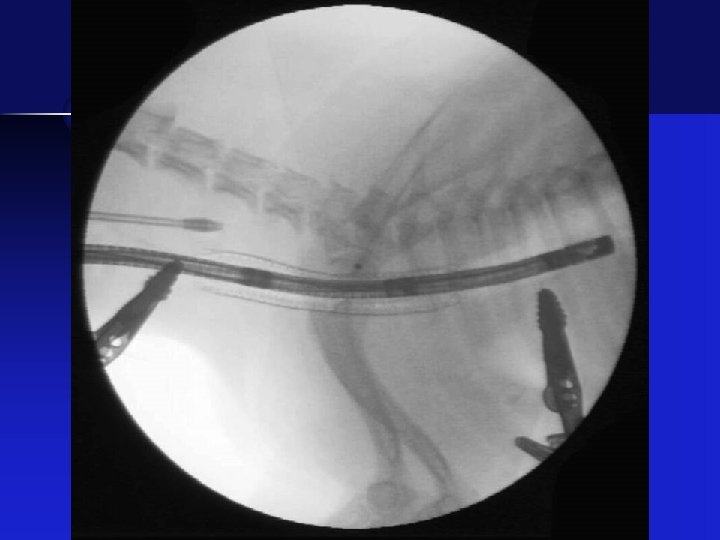

Stent Placement • Stent deployed under fluoroscopic guidance • Target – 5 mm cranial to bifurcation • Placement checked with tracheoscopy

Stent in Place